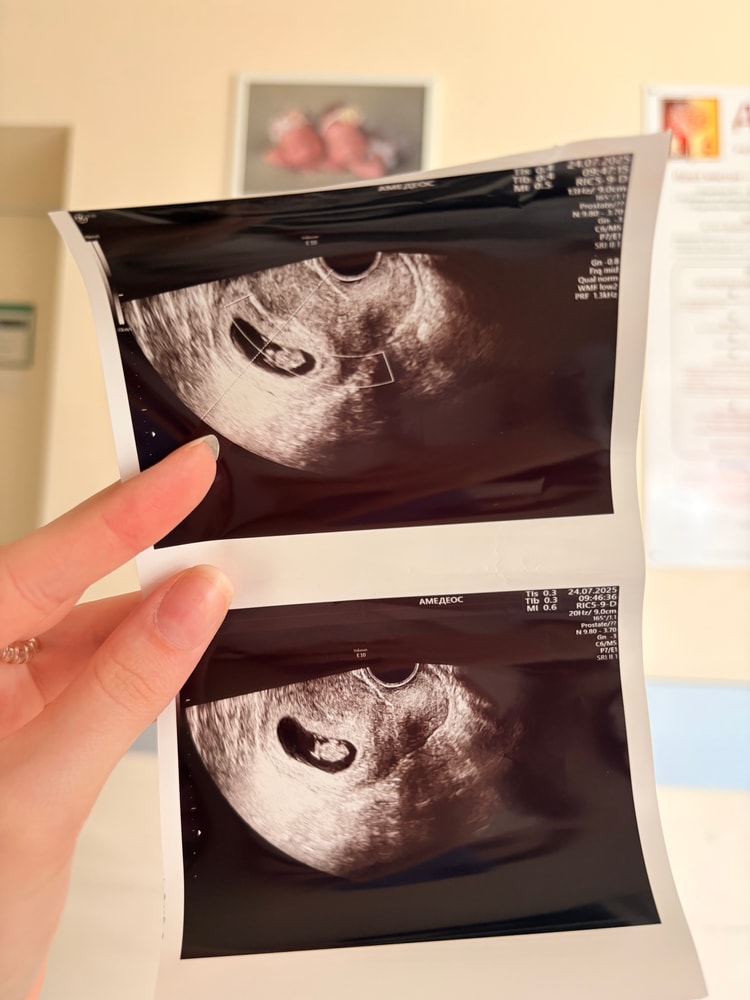

8 недель и 3 дня🤗

Беременность- 1 триместр ( только до 10 недель)

ЧСС – 157 уд/мин. Плодное яйцо, КТР – всё соответствует сроку.